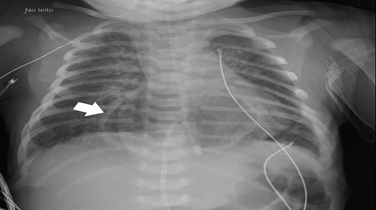

Male newborn, born to a G4P4 mother in her 40s, without previous history of miscarriages, familial malformation syndromes or parental consanguinity. Pregnancy was uncomplicated. However, an ultrasound at 32 weeks gestation revealed an anechogenic formation posterior to the fetus’ heart, suggestive of an intrathoracic stomach, without pulmonary hypoplasia. Magnetic resonance imaging at 35 demonstrated the same structure, contiguous to the esophagus, with a tubular morphology and liquid content compatible with a hiatal hernia (figure 1). Additionally, a fetal echocardiogram at 35 weeks showed an aortic isthmus narrowing (3mm in the sagittal plane, z-score -2.4). The neonate was born at 39 weeks via spontaneous noncomplicated vaginal delivery. Because of the known gastric hernia, nasotracheal intubation was tried immediately after birth. However, the baby showed no respiratory compromise, with spontaneous breathing and normal oxygenation, so further attempts were not performed. He was in good condition at birth with Apgar scores of 9 at one minute and 10 at five and ten minutes. On examination, generalized wrinkled and redundant skin were noted, more prominently involving the face, eyes, and limbs (figure 2), giving an aged appearance. Additional findings included small palpebral fissures, palmar hyperlinearity, inverted nipples, and increased inter-nipple distance.

Figure 1: Fetal Magnetic Resonance Imaging (MRI) at 35 weeks: A structure with fluid signal is in a medial location (arrow) posterior to the heart, with a tubular morphology and contiguity with the esophagus. This structure measures 35 x 20 x 25 mm and has a thin, regular wall with folds inside, compatible with a herniated stomach.

Upon admission to the pediatric intensive care unit, thoracoabdominal radiography (figure 3) and abdominal ultrasound demonstrated a partially intra-thoracic stomach, suggesting of a hiatal hernia with preserved diaphragm continuity. Echocardiogram revealed aortic isthmus narrowing with a maximum systolic gradient of 12 mmHg. The neonate was under continuous cardiorespiratory monitoring, and blood pressure, diuresis, and temperature were evaluated every four hours. He was breathing spontaneously with no signs of respiratory distress and had a nasogastric tube in passive drainage.

Figure 3: Thoracic and abdominal radiography on day 1 showing herniated intrathoracic stomach (arrow).